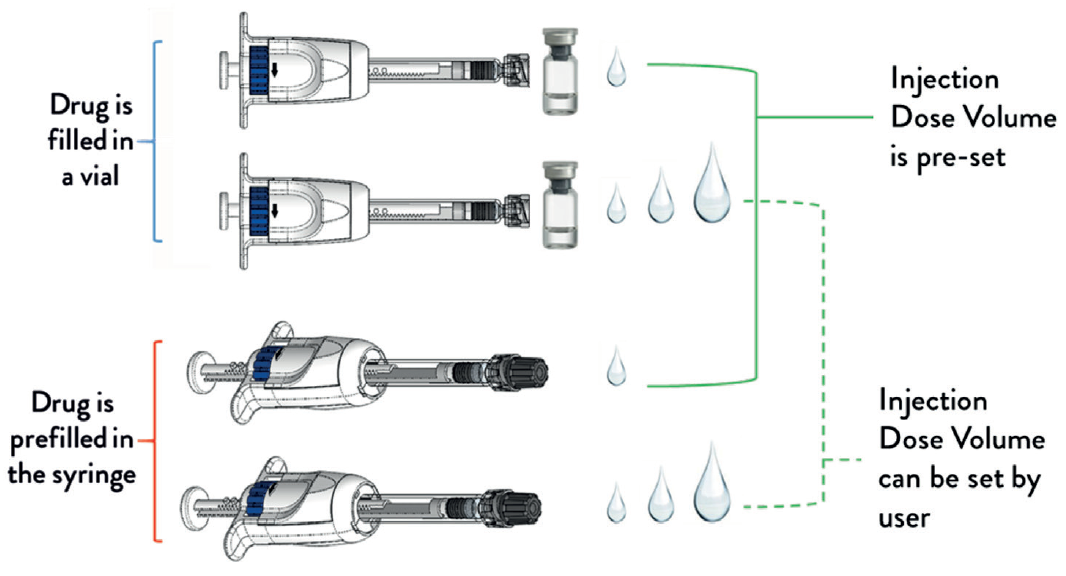

GS The MDS platform can be made available as a prefilled syringe format or so that drug can be filled from a vial, and its injection dose volume can be preset by the manufacturer, or set by the user. This gives four different combinations of configurations (Figure 4). The MDS in its non-prefilled configuration enables a prefillable syringe to be paired with a vial-filled drug. We have initiated submission of the MDS for US FDA 510k premarket clearance. expect in 2020 the MDS will be available for use in drug clinical trials or drug commercial sales.

Figure 4: The MDS platform can be made available in four different configurations.